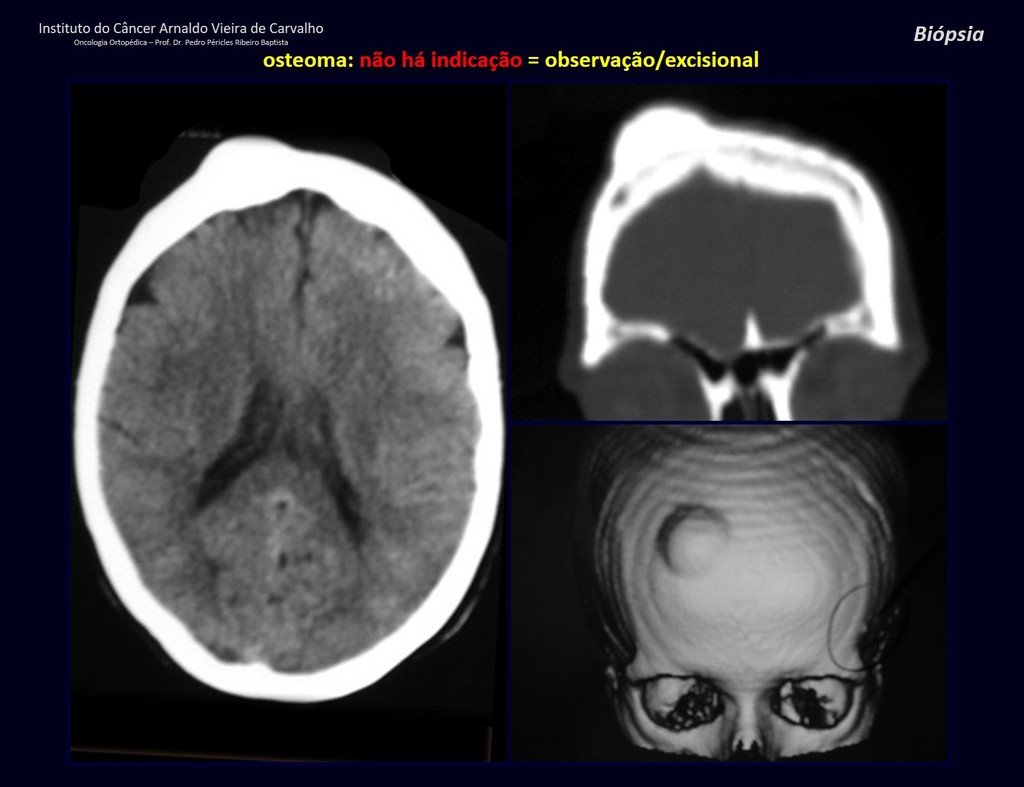

Biópsia – Conceito – Tipos – Indicações – Planejamento